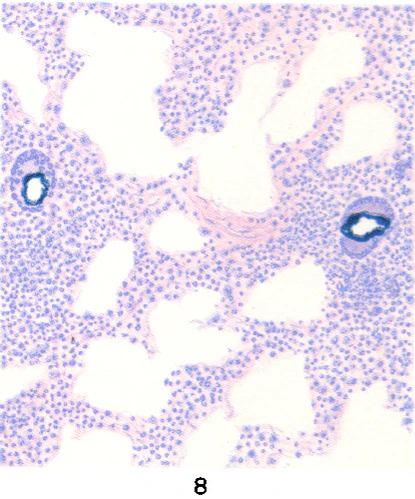

При бериллиозе морфологические изменения характеризуются диффузным поражением обоих лёгких и плевры, распространённым гранулёматозом и хроническим межуточным (синоним «промежуточный») пролиферативным процессом, локализующимся в перегородках альвеол, под плеврой, перибронхиально, периваскулярно. Гранулёмы — серовато-белого цвета, плотной консистенции, размером от 0,2 до 1,5 см. Гранулёма состоит в основном из гистиоцитов, эпителиоидных клеток с примесью (главным образом по периферии) лимфоидных, плазматических и гигантских клеток типа клеток инородных тел (цветн. рис. 4—9). Гигантские клетки содержат кристаллические образования. В дальнейшем происходит созревание клеток гранулёмы с появлением в ней фибробластов. Фибробласты начинают продуцировать коллагеновые волокна, и процесс завершается развитием на месте гранулёмы соединительнотканного узелка, который нередко подвергается гиалинозу. В гранулёмах обнаруживают типичные для Б. конхоидальные (раковинообразные) тельца диаметром от 2,5 до 10 мкм, которые могут образовывать скопления диаметром до 190 мкм. Иногда они располагаются в многоядерных гигантских клетках. Конхоидальные тельца окрашиваются гематоксилином в синий, сине-фиолетовый цвет, иногда дают положительную реакцию на железо, имеют вид флюоресцирующих голубоватых зёрен при освещении ультрафиолетовыми лучами. Наряду с гранулёматозом в межальвеолярных перегородках наблюдается диффузный пролиферативный процесс с наличием гистиоцитов, лимфоидных, плазматических клеток, фибробластов, заканчивающийся диффузным пневмосклерозом. Наблюдается бронхит, возможно развитие бронхоэктазов. Встречаются участки ателектаза и эмфиземы. В кровеносных сосудах могут иметь место эндартериит, эндофлебит, тромбозы. Описанные изменения в лёгких обычно приводят к развитию лёгочного сердца[6].